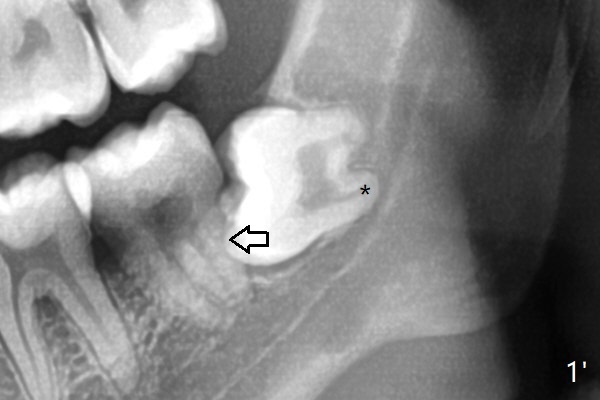

A 22-year-old man agrees with extraction of #16 and 17 with bone graft in the latter socket (Fig.1). Because of horizontal impaction, the mesial root tip (Fig.1' *) overlaps with the Inferior Alveolar Canal. 5x5 cm CT will be taken with special bite block to show the ramus as posterior as possible (internal and external oblique ridges). Since the crown of the 3rd molar seems to be buccal to the distal portion of the 2nd molar, the anterior oblique incision should be placed as mesial as possible (Fig.2 red line). After extraction, collagen plug (Fig.3 large white area) will be inserted into the root sockets, while sticky bone (circles) in the coronal socket. The latter will be covered by 2 pieces of PRF membrane, followed by compressed Osteogen Plug (small white area, tp be visible in the postop panoramic 2 bitewings).